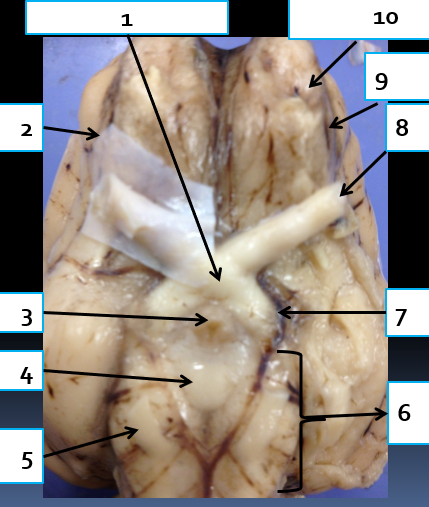

1

pons, connects cerebrum with lower CNS centers

2

abducens nerve, CN6, eye muscle control

3

spinal cord, reflex area

4

medulla oblongata, controls vital autonomic functions like heart rate

5

trigeminal nerve, CN5, motor control of jaw muscles

6

trochlear nerve, CN4, eye muscle control

7

cerebral peduncle, connects cerebrum to pons

8

oculomotor nerve, CN3, eye muscle control